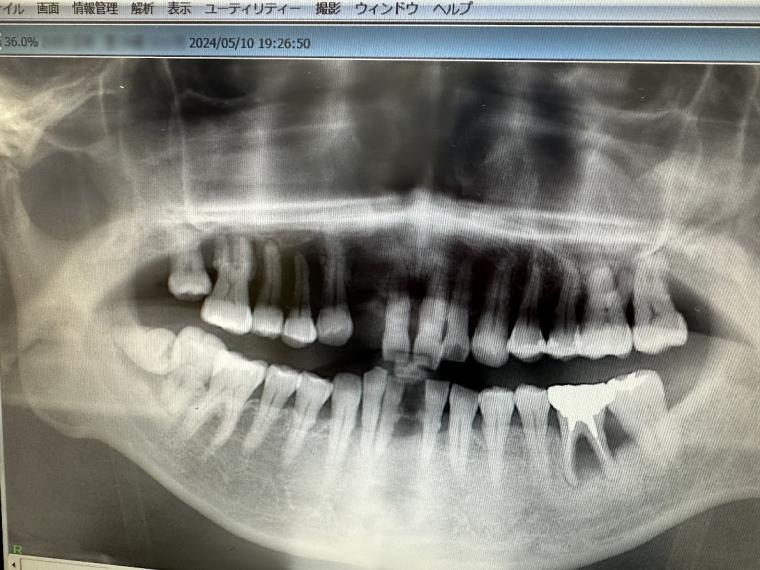

(2024年)

その影響もあり、気づかないうちに

歯がだいぶ抜け、骨もなくなってしまいました。